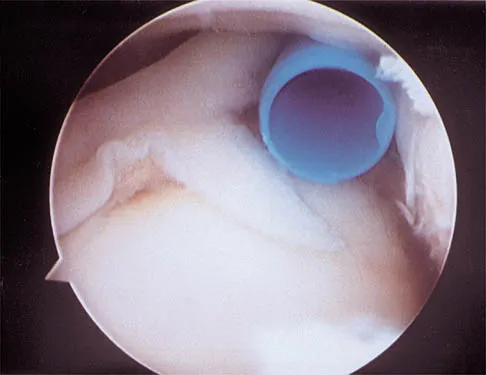

Question 99High Yield

A 21-year-old collegiate pitcher has had pain in his dominant shoulder for the past 3 months despite management consisting of rest, rehabilitation, and an analysis of throwing mechanics. An arthroscopic photograph from the posterior portal is shown in Figure 10. The biceps anchor to the bone was not detached to probing. Treatment of the lesion to the left of the cannula should consist of arthroscopic

Explanation